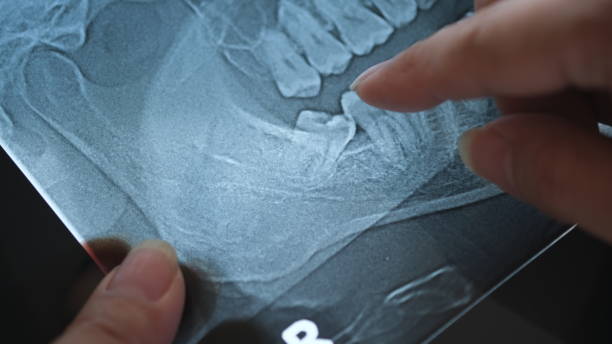

사랑니 발치를 앞두고 있거나 이미 발치한 분들이 가장 궁금해하는 것 중 하나가 바로 '뭘 먹어야 할까?' 그리고 '통증을 어떻게 줄일 수 있을까?' 하는 점일 텐데요.

오늘은 사랑니 발치 후 추천 식사 메뉴와 통증 줄이는 방법에 대해 자세히 알려드리겠습니다!